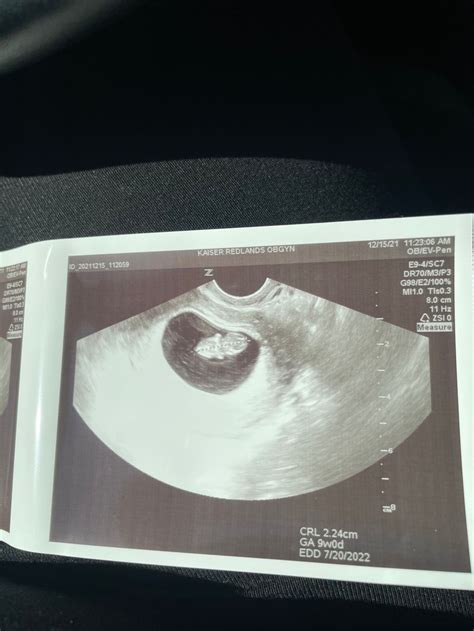

A 9 weeks pregnant ultrasound is typically performed to assess the baby's growth and development. At this stage, the ultrasound can provide detailed images of the fetus, allowing healthcare providers to measure the baby's size, check for a heartbeat, and evaluate the overall health of the pregnancy. This scan is usually done transabdominally, meaning the ultrasound probe is moved over your belly, or transvaginally, where the probe is inserted into the vagina for a clearer view.

• Crown-Rump Length (CRL): The measurement from the top of the head to the bottom of the buttocks, which helps to estimate the baby's age and growth.

📝 Note: The crown-rump length is a crucial measurement that helps healthcare providers determine the baby's gestational age and ensure that development is progressing normally.

After the 9 weeks pregnant ultrasound, your healthcare provider will review the images and measurements. They will look for:

• Normal Development: Ensuring that the baby's organs, limbs, and facial features are developing as expected.

• Heartbeat: Confirming a strong and regular heartbeat.

• Growth: Checking that the baby's size is appropriate for the gestational age.